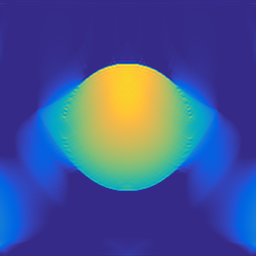

A 2D scenario: Ω=[0,1]2Ωsuperscript012\Omega=[0,1]^{2} with inhomogeneous medium properties and an irregular sensor geometry, see Figure 1. The medium properties vary in the range encountered, e.g., in the human breast [19].

Figure 1: 2D PAT scenario (II) used in the numerical studies. The spatial resolution is N=5122𝑁superscript5122N=512^{2} plus 242424 pixels of PML layer in all directions. LABEL:sub@subfig:2DScenarioA The scenario cosists of three materials: Material A (covering the top part of the domain): c=1500𝑐1500c=1500, ρ0=1000subscript𝜌01000\rho_{0}=1000, material B (parabolic-like part): c=1400𝑐1400c=1400, ρ0=1200subscript𝜌01200\rho_{0}=1200, material C (vessel-like part): c=1560𝑐1560c=1560, ρ0=800subscript𝜌0800\rho_{0}=800. LABEL:sub@subfig:2DScenarioB Ground truth p0subscript𝑝0p_{0} and sensor configuration (white pixels, 200200200 sensors at the interface between materials A and B.)